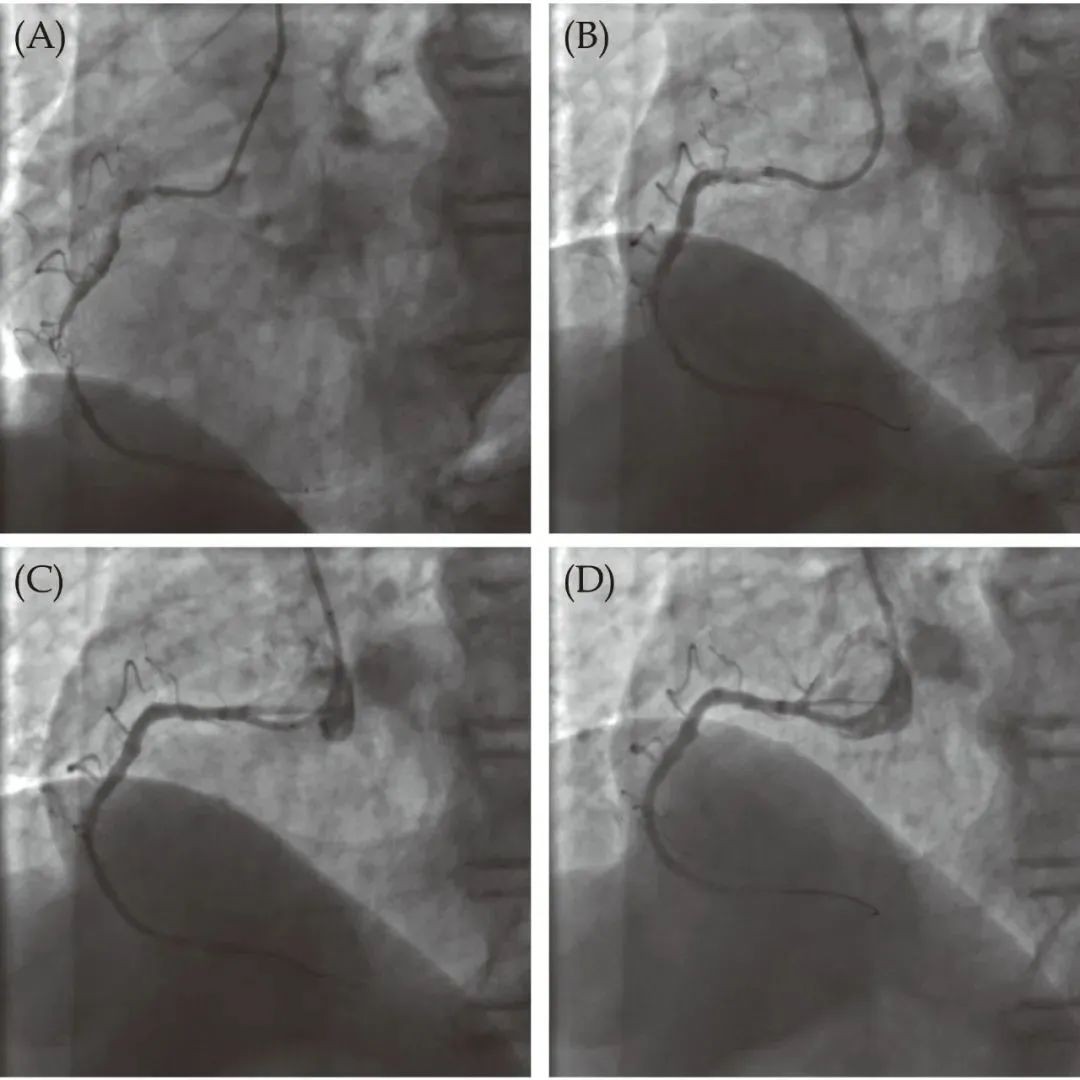

The PCI images of a robotic-assisted system for patients:

A: Angiographic images before PCI using a robotic-assisted system

B: Pre-dilation image

C: Image after stent placement

D: Post-dilation image